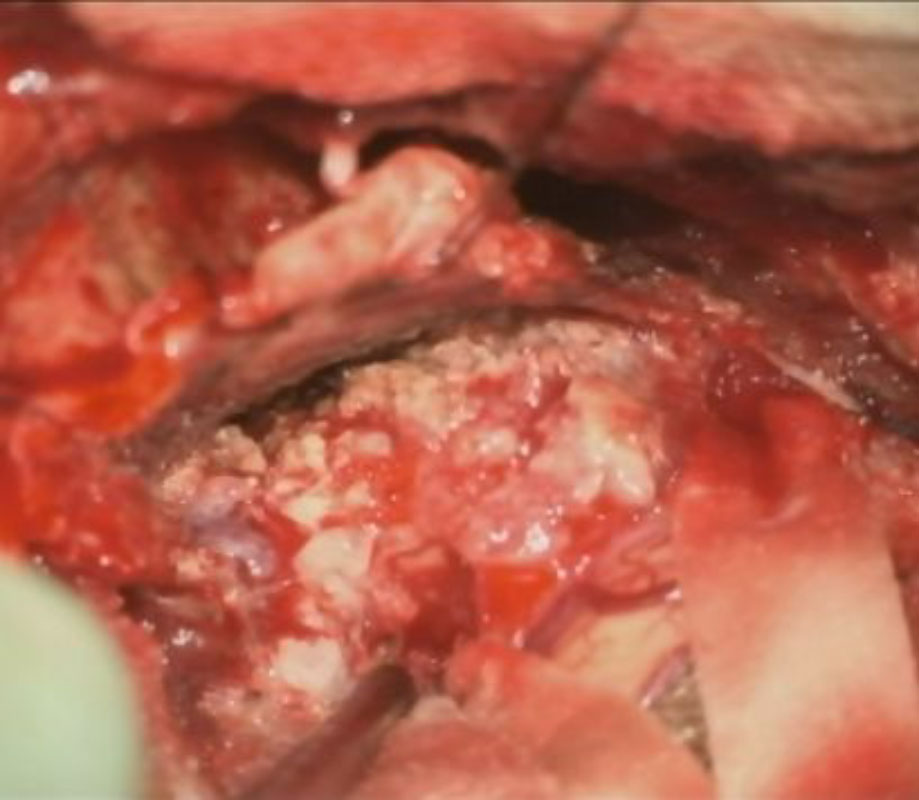

摘出 前

摘出 中

摘出 後